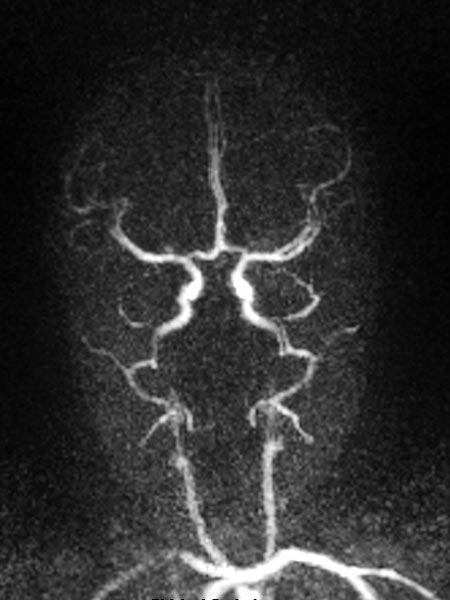

Dynamic contrast-enhanced MR angiography of the skull and cerebral vessels. In the very early arterial phase (A) no yet enhancement of the lesion in the left eye.

Dynamic contrast-enhanced MR-angiography in the arterial phase, 5 seconds later, depicts early and intense enhancement of the tumor in the left eye.

Dynamic, contrast-enhanced MR angiography, early venous phase. The strong enhancement remains, venous drainage via the facial veins and the left-sided external jugular vein.